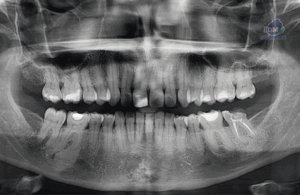

Caso 335 – IDM – TORUS LINGUAL – IDM

Paciente masculino de 67 años de edad, es referido al Instituto de Diagnóstico Maxilofacial – IDM para control tomográfico.En la radiografía panorámica (Figura 1), se